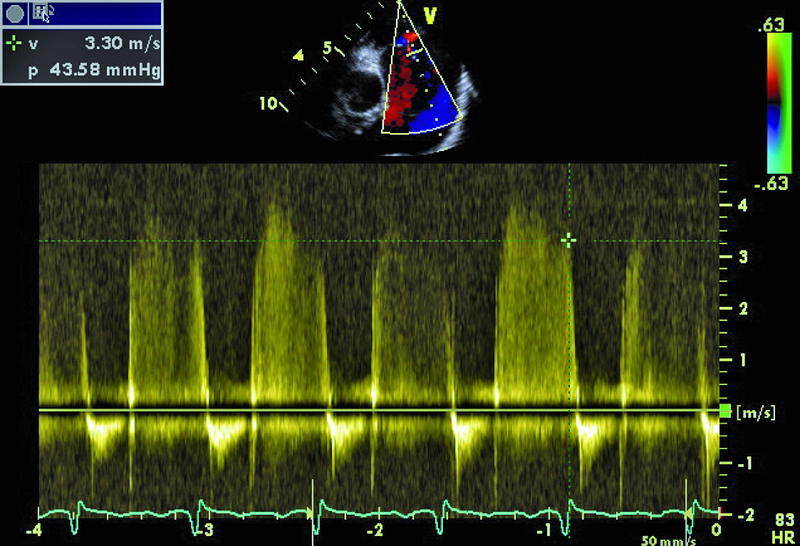

U chłopca, obecnie 16-letniego, wykonano w okresie noworodkowym zabieg operacyjny walwuloplastyki zastawki aortalnej z powodu wrodzonej stenozy. Uzyskano zmniejszenie gradientu maksymalnego z 50 do 16 mm Hg. W ciągu wielu lat obserwacji w ośrodku kardiologii dziecięcej gradienty przepływu przez zastawkę były niskie, a stan kliniczny pacjenta dobry. Sytuacja zmieniła się przed kilkoma miesiącami. Chłopiec został przyjęty do szpitala z powodu męczliwości, szybkiej częstości serca (do 90/min w rytmie zatokowym z pojedynczą ekstrasystolią komorową). Prawdopodobną przyczyną pogorszenia stanu zdrowia była przebyta wcześniej infekcja górnych dróg oddechowych. W badaniu przedmiotowym zwracał uwagę szmer holosystoliczny na koniuszku, promieniujący do pachy. W EKG rejestrowano cechy przerostu i przeciążenia mięśnia lewej komory. Wykonano cewnikowanie serca, stwierdzając nadciśnienie płucne ze średnim ciśnieniem w kapilarach płucnych 29 mm Hg. Pacjent był leczony intensywnie lekami moczopędnymi, beta-adrenolitykami i amiodaronem. Wobec braku poprawy skierowano go na oddział kardiologii dorosłych w celu rozważenia wskazań do leczenia operacyjnego. W badaniu echokardiograficznym zwracały uwagę wąskie strumienie niedomykalności zastawki aortalnej z czasem PHT wynoszącym 206 ms, istotnie powiększona jama lewego przedsionka z powierzchnią około 50 cm2, ciężkie nadciśnienie płucne z ciśnieniem skurczowym w jamie prawej komory 114 mm Hg!, rejestrowanym z małej fali zwrotnej trójdzielnej. Nie stwierdzono wady przeciekowej.

Chłopiec przebył w okresie noworodkowym zabieg walwuloplastyki aortalnej powikłany niedomykalnością zastawki (ryc. 1). Wada miała charakter przewlekły i spowodowała pojawienie się mechanizmów wyrównawczych. Jednym z nich jest zwiększenie objętości lewej komory i przyspieszenie rytmu serca. Frakcja wyrzutowa lewej komory jest zachowana (ryc. 2). Z pewnością infekcja górnych dróg oddechowych była czynnikiem inicjującym niekorzystny dla chorego przebieg zdarzeń. Ocena ciężkości niedomykalności aortalnej na podstawie parametrów ilościowych jest w tym przypadku trudna. Czas połowicznego spadku gradientu ciśnień PHT (aorta – lewa komora) oraz strumień fali zwrotnej w badaniu kolorowego doplera mogłyby wskazywać na umiarkowaną niedomykalność. Nie można jednak zapominać o możliwości zwiększenia ciśnienia rozkurczowego w jamie lewej komory, istotnie zmniejszającego gradient wsteczny i zakres fali zwrotnej. W przypadku dwustrumieniowej fali zwrotnej (jak w tym przypadku) talii cząstkowych niedomykalności nie sumuje się. Podobnie ograniczone zastosowanie w tym wypadku (ekscentryczne fale zwrotne) ma metoda ERO. Najprawdopodobniej wtórną do niedomykalności aortalnej wadą jest niedomykalność mitralna wynikająca z poszerzenia jamy lewej komory i poszerzenia pierścienia zastawki mitralnej. Niedomykalność mitralna także wydaje się co najwyżej umiarkowana (ryc. 3). Należy pamiętać, że i w tym wypadku szerokość strumienia fali zwrotnej zależy od wysokości ciśnienia w jamie przyjmującej, czyli w lewym przedsionku. Na podstawie przedstawionego materiału (ryc. 4-6) można stwierdzić, że nadciśnienie płucne u chłopca (postkapilarne) jest ciężkie, a ciśnienia uległy istotnemu zwiększeniu w porównaniu z wartościami stwierdzanymi wcześniej podczas cewnikowania serca (ciśnienie rozkurczowe płucne 54 mm Hg, średnie 74 mm Hg!). Warto zwrócić uwagę na profil spływu z żył płucnych. Zaznacza się w nim bardzo krótka faza odzwierciedlająca wyłącznie rozkurczowy napływ krwi do lewego przedsionka. Zwiększona objętość jamy przedsionka, wysokie ciśnienie krwi w niej panujące oraz ograniczona podatność ściany sprawiają, że w fazie skurczu komory nie rejestruje się napływu do jamy przedsionka. Podobnie bardzo wysokie ciśnienie w układzie żył płucnych sprawia, że nie obserwuje się przepływu wstecznego w związku z ciągle zachowanym skurczem przedsionka (rytm zatokowy). Chłopca zakwalifikowano do operacji dwuzastawkowej z powodu ciężkiej niedomykalności aortalnej i mitralnej. Zabieg implantacji zastawki biologicznej o średnicy 23 mm w ujście aortalne oraz pierścienia o średnicy 32 mm w ujście mitralne przyniósł dobry efekt.